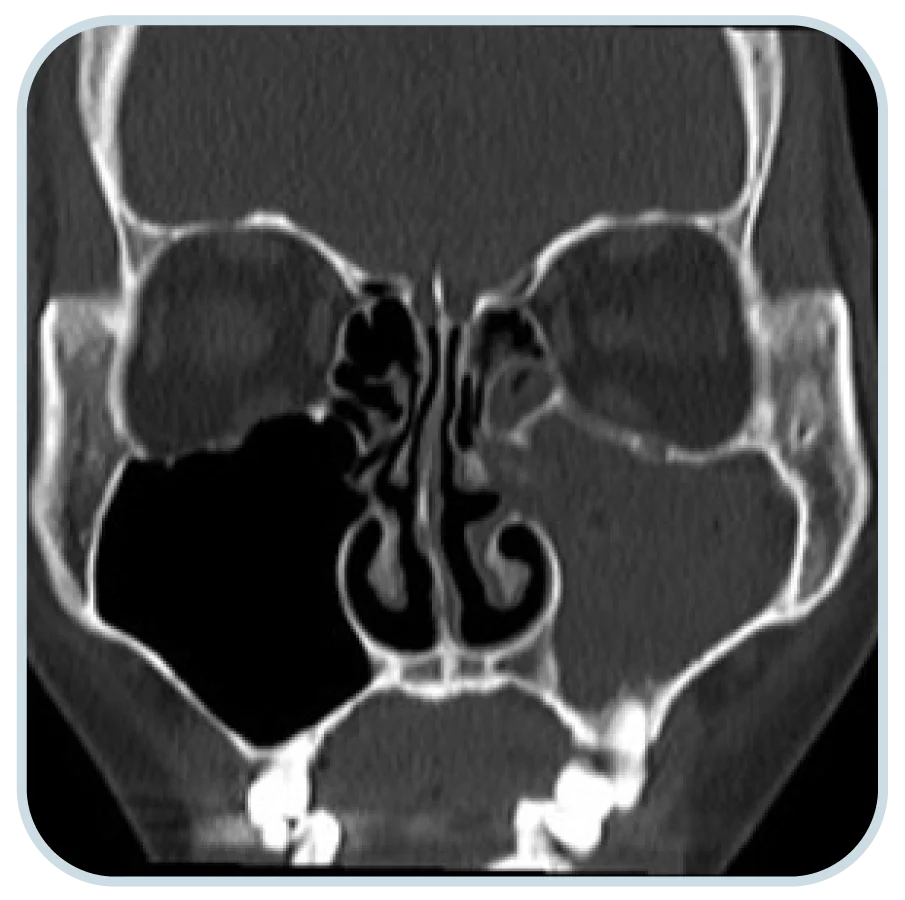

鼻竇電腦掃描